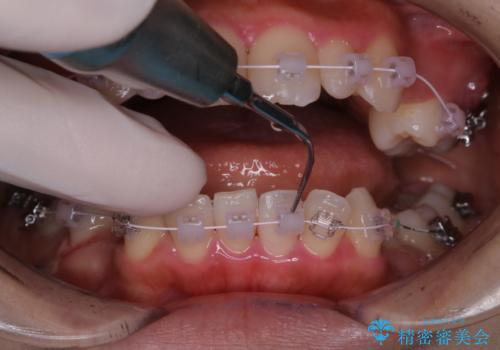

ワイヤー矯正中のクリーニング PMTC

- ワイヤー矯正中にクリーニングを行いたいとのことで来院されました。PMTC60分コースでと歯磨き指導も行いました。

ワイヤー矯正中はブラッシングが難しくなるため、磨き残しが多くなることがあります。適切な道具を使って、適切なブラッシング方法を習得することで、磨き残しを減らすことができます。

また、矯正で歯の移動があると今までなかったところに隙間が出てきたり、ガタつきが解消されてきたりすることで、お口の中の環境が変わります。そのため、定期的に専門的な機械・材料を使用したProfessinnalcleaning(pmtc)を行うことがおススメです。